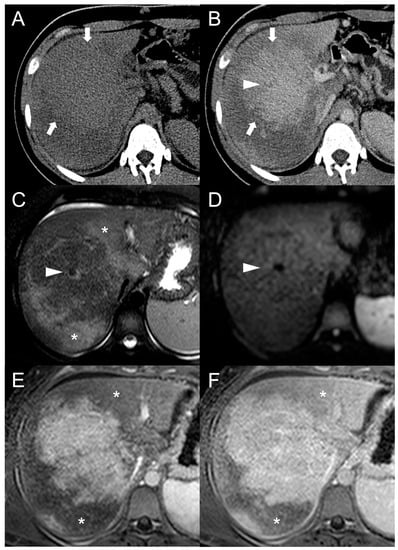

Being composed of nearly normal hepatocytes, >95% of FNH-like RNs are isodense to surrounding parenchyma on nonenhanced CT imaging (Figure 1A) [14]. In some cases, when located in the subcapsular region, they may be detected due to the alteration of liver contours. More rarely, they may appear hyperdense or hypodense compared to the liver.

Figure 1.

CT examination of 36-years-old male patient with Budd–Chiari syndrome. On unenhanced images (A), the liver parenchyma appears relatively homogeneous, and the presence of TIPS stent (arrowhead) and perihepatic ascites (asterisks) can be observed. On arterial phase (B), multiple homogeneously enhancing FNH-like RNs can be visualized in the liver (arrows), some exhibiting a hypodense perinodular rim (arrowhead) due to atrophic hepatic tissue with congested sinusoids. In both portal venous (C) and delayed phase (D), the regenerative nodules (arrows) become iso-dense or slightly hyperdense compared to the surrounding inhomogeneous liver parenchyma, making them difficult to detect.

After iodine contrast administration, the nodules are well evident on arterial phase images because they are hypervascularized, hence showing marked and homogeneous contrast enhancement in almost all cases (Figure 1B). Hypervascularization is atypical in cirrhotic regenerative nodules, but in FNH-like RNs associated with BCS it probably represents a compensatory response to regional loss of portal flow. On the portal and late venous phases, the FNH-like RNs usually remain isodense or slightly hyperdense (Figure 1C,D). A hypodense perinodular rim may also be observed on contrast enhanced CT imaging because of the presence of atrophic hepatic tissue around the nodule with sinusoidal congestion.